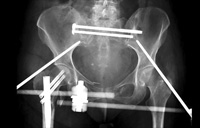

External fixation. Your doctor may use external fixation to stabilize your pelvic area. In this operation, metal pins or screws are inserted into the bones through small incisions into the skin and muscle. The pins and screws project out of the skin on both sides of the pelvis where they are attached to carbon fiber bars outside the skin. The external fixator acts as a stabilizing frame to hold the broken bones in proper position.

In some cases, an external fixator is used to stabilize the bones until healing is complete. In patients who are unable to tolerate a lengthy, more complicated procedure, an external fixator may be used as a temporary treatment until another procedure can be performed.

In this x-ray, an external fixator has been used to stabilize the pelvis.

Reproduced from Kurylo JC, Tornetta P: Initial management and classification of pelvic fractures. Instructional Course Lecture 61. Rosemont, IL, American Academy of Orthopaedic Surgeons, 2012, pp. 3-18.